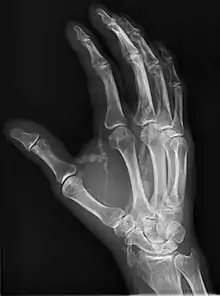

Hand radiograph showing tumoral calcinosis, PA radiograph of the right hand showing tumoral calcinosis-like metastatic calcification in a patient on dialysis. Dialysis alters calcium phosphate product (>70). Idiopathic tumoral calcinosis is autosomal dominant and is not associated with dialysis. Note the premature arterial calcification which is a clue that this is a renal patient. Vascular calcification contributes to an increase in morbidity. |

Tumoral calcinosis is a rare condition in which there is calcium deposition in the soft tissue in periarticular location, around joints, outside the joint capsule.[1] They are frequently (0.5–3%) seen in patients undergoing renal dialysis. Clinically also known as hyperphosphatemic familial tumoral calcinosis (HFTC), is often caused by genetic mutations in genes that regulate phosphate physiology in the body (leading to too much phosphate (hyperphosphatemia)). Best described genes that harbour mutations in humans are FGF-23,[2] Klotho (KL),[3] or GALNT3.[4] A zebrafish animal model with reduced GALNT3 expression also showed HFTC-like phenotype,[5] indicating an evolutionary conserved mechanism that is involved in developing tumoral calcinosis.